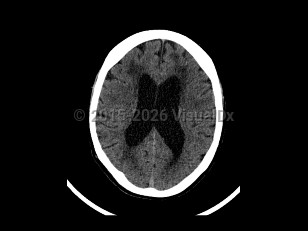

Normal pressure hydrocephalus (NPH) is a common neurologic disorder resulting in slowly progressive gait abnormalities, cognitive deterioration, and urinary incontinence.

The syndrome is often divided into 2 groups, idiopathic and secondary, based on etiology. Idiopathic NPH is thought to occur due to increased resistance to cerebrospinal fluid (CSF) absorption, leading to temporary elevations in intracranial pressure and mechanical compression of structures adjacent to the ventricles. However, the underlying etiology of idiopathic NPH has not yet been identified. Secondary causes of NPH include the sequelae of brain infections such as meningitis, trauma, or subarachnoid hemorrhage. This article will focus on the diagnosis, evaluation, and treatment of idiopathic NPH.

Approximately 40%-75% of patients with suspected NPH are subsequently found to have other comorbid neurodegenerative diseases such as Alzheimer disease. NPH patients with other comorbid neurodegenerative conditions are thought to have a poorer response to CSF shunting.